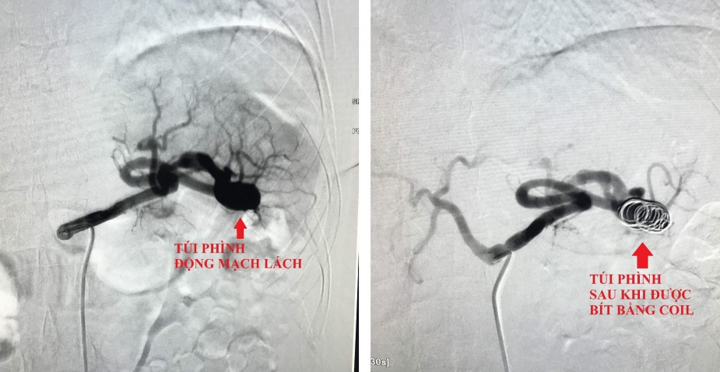

Người phụ nữ đau bụng âm ỉ kéo dài, đi khám phát hiện bị phình động mạch lách, nếu chỗ phình bị vỡ có thể gây tràn máu toàn ổ bụng, nguy cơ tử vong cao.